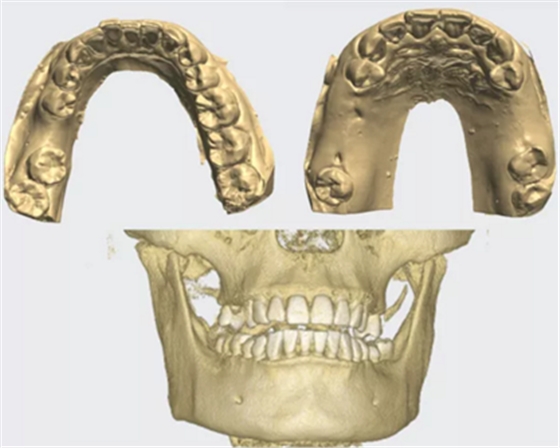

CT與模型

CBCT數(shù)據(jù)與模型數(shù)據(jù)整合